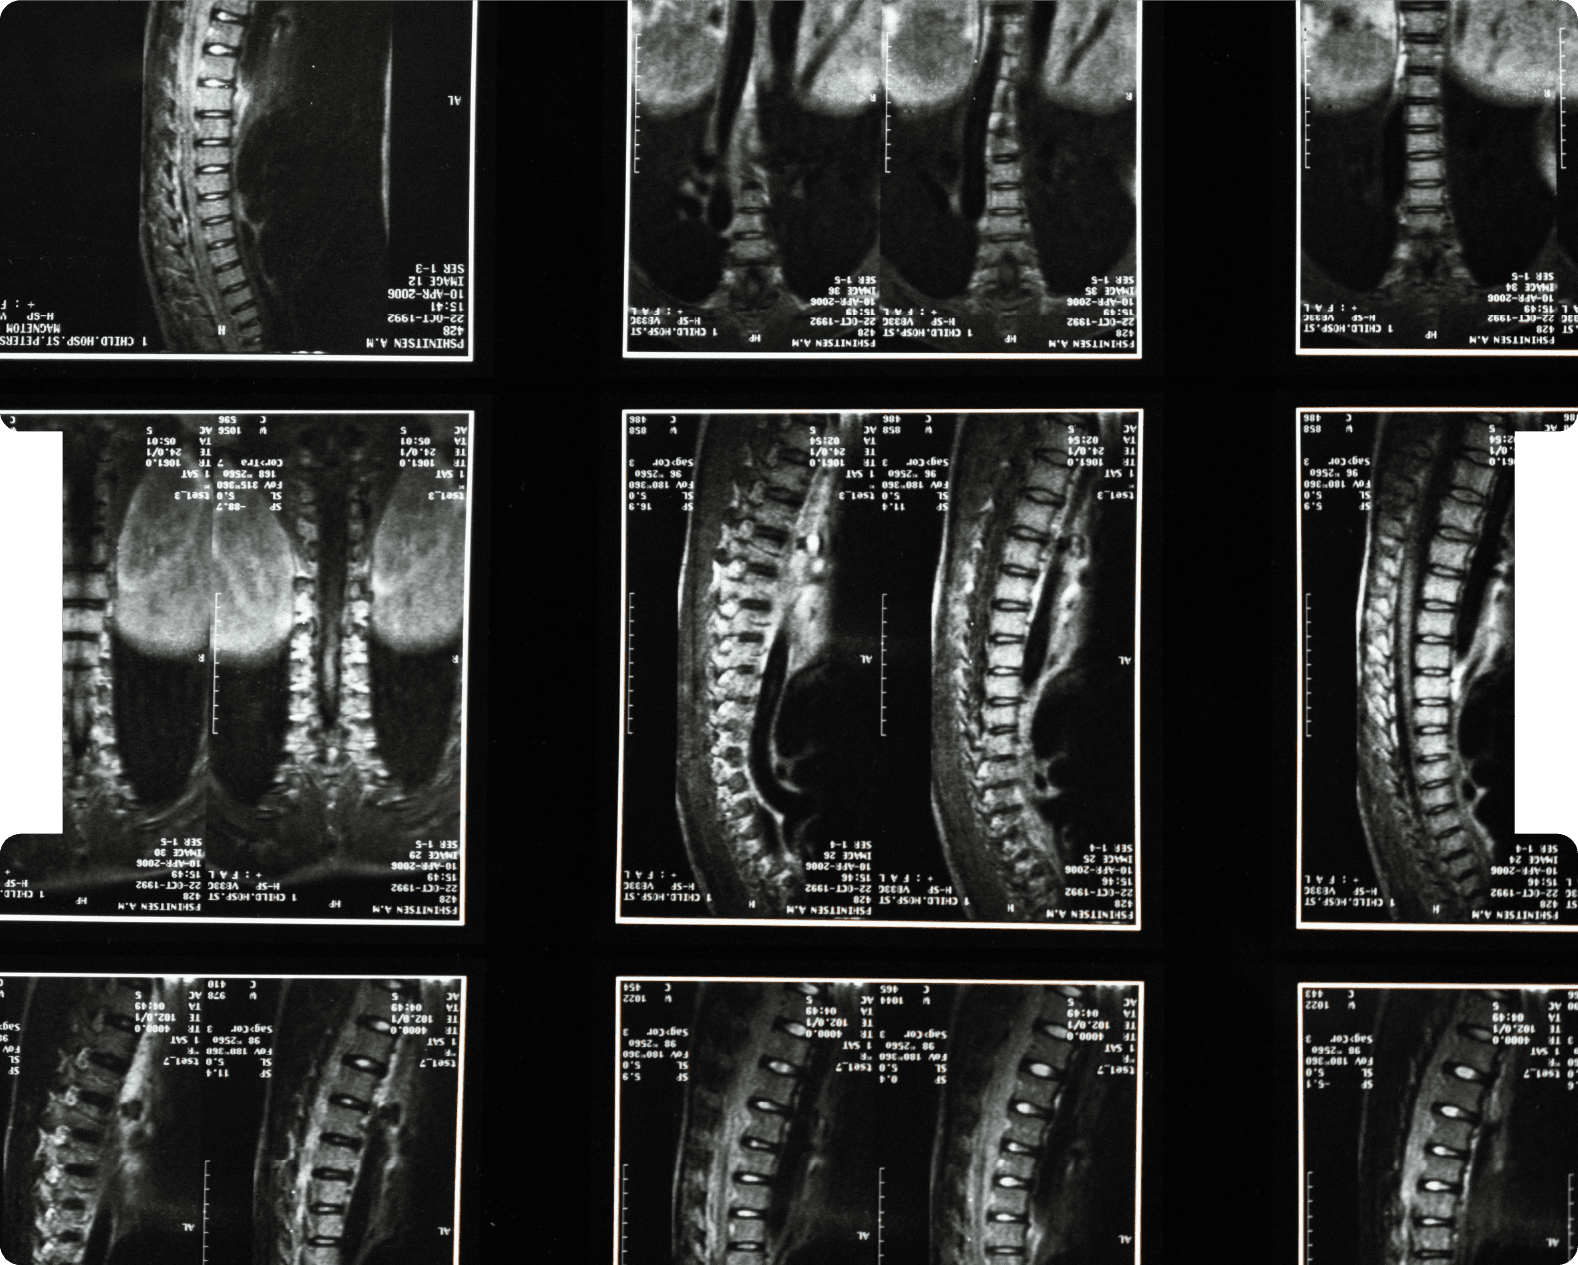

Neuroradiology

51

Neurosurgery

214